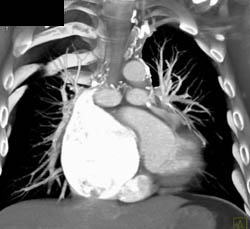

Dilated Aortic Root